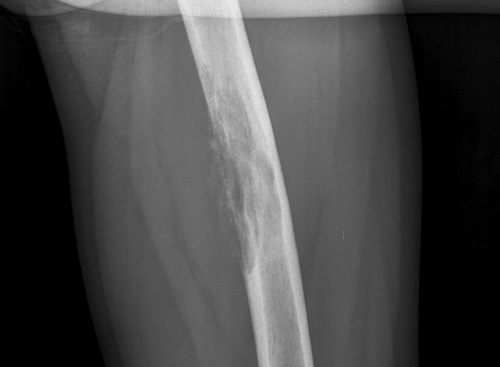

- Компьютерная томография и рентгенографические исследования кости бедра. Они позволят с высокой достоверностью подтвердить деструкцию костной структуры.